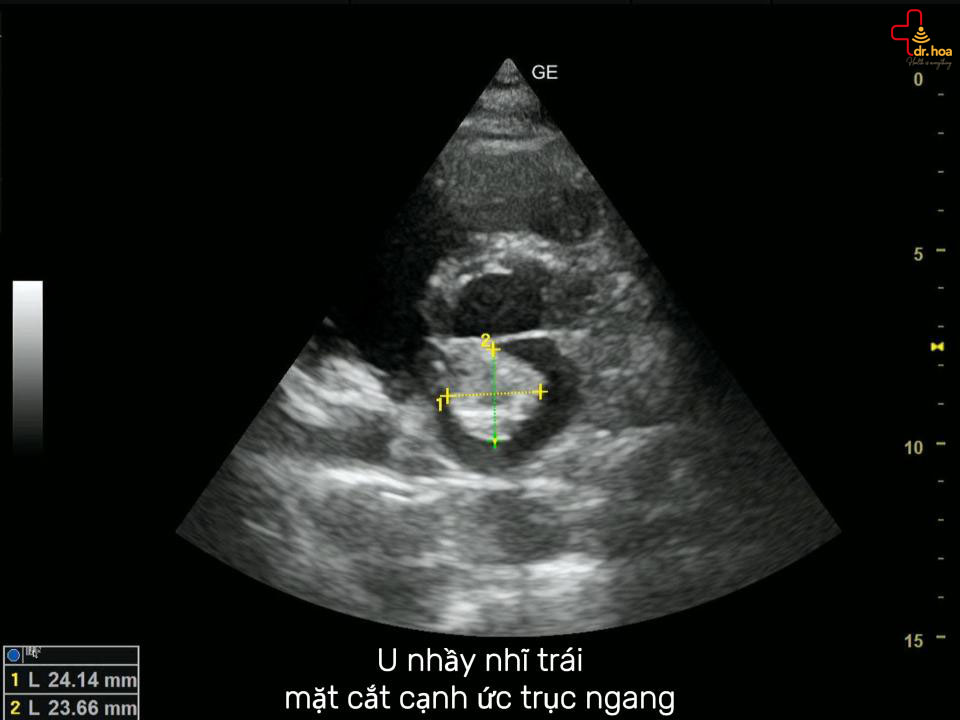

U nhầy nhĩ trái, mặt cắt cạnh ức trục ngang. U nhầy nhĩ trái, mặt cắt cạnh ức trục ngang.

• Siêu âm tim:

Đây là kỹ thuật quan trọng và được sử dụng phổ biến nhất. Siêu âm tim giúp xác định rõ vị trí, kích thước, chỗ bám cũng như đặc điểm cấu trúc của khối u nhầy (có thể đồng nhất, chứa nang hoặc vôi hóa). U nhầy nhĩ trái, động mạch chủ cắt ngang. U nhầy nhĩ trái, động mạch chủ cắt ngang.